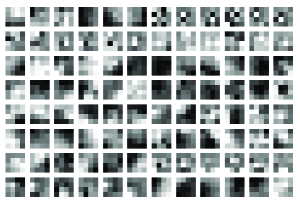

The features (filters) learned by the first and second convolutional layers of CNN corresponding to the th epoch trained with rotated cell images are depicted as Fig. 9. It can be seen that the filters of the first convolutional layer are stain-like texture detectors. Some of the second convolutional layer filters are edge-like detectors, and most of them are also stain-like texture extractors.